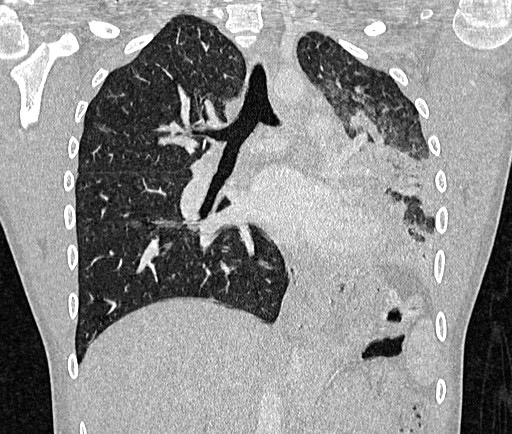

На КТ спостерігається ендобронхіальне утворення в проксимальному відділі лівого головного бронху з дистальним ателектазом. Утворення не має порожнин та вогнищ кальцифікації.

Висновок: хворій було виконано лобектомію та гістологічно було доведено, що це типова карценоїдна пухлина.